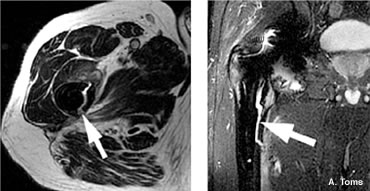

MoM bearing surfaces have encountered varied results over the years. The ability of offering larger diameter heads has increased the usage of MoM as one of the mechanisms to reduce hip dislocations. However, issues have been raised with regards to cup spinout, high trace elements, and metal sensitivity.

| MOM Bone Necrosis - A. Toms |

L. Keppler - cup spin out 7 weeks post-op |

MoM cup migration 2 years post-op |